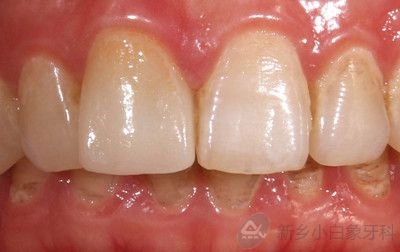

2015年8月16号二期修复结束。

治疗后